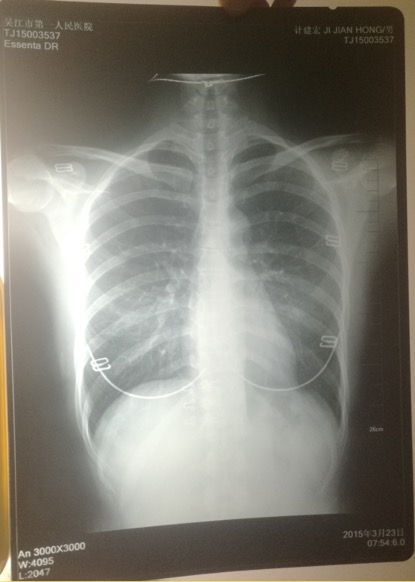

印有計建宏姓名的胸片實為一名女性的。 受訪者供圖

印著父親姓名的胸片,圖像卻顯示有明顯女性文胸搭扣和項鏈的印記。

“當時我和母親都奇怪,一年多前體檢正常,怎么這么快腫瘤長得如此大了?”更令計云強疑惑的是,該院胸外科主任在系統中輸入計建宏姓名后,查詢得到的胸片,可明顯看出有女性文胸的搭扣和項鏈,“后來醫生含糊地說可能是同名同姓,便不讓我看了。”

“7月初,我們回到吳江,帶著滿心悲傷和疑慮去了體檢科,想搞清楚父親的胸片究竟是怎么回事。”計云強稱,此后幾經周折,在找了吳江區第一人民醫院體檢科、投訴科等多個部門后,耗時多月,才被體檢科通知去拿父親的胸片,“一張是我父親的名字,但有文胸印記;另一張是醫院所謂的我父親的胸片,顯示的是其他人的姓名。”